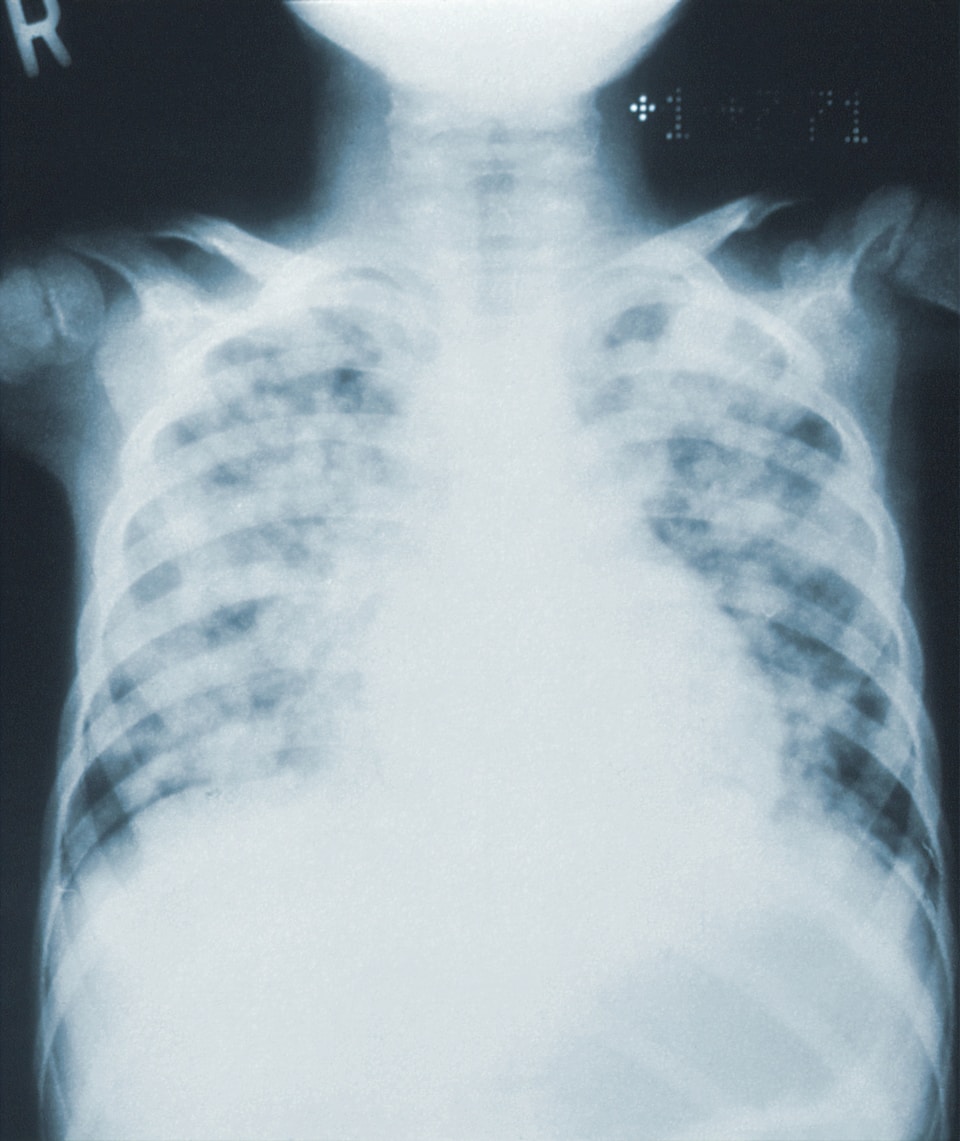

निमोनिया वयस्कों और बच्चों की सबसे बड़ी संक्रामक बीमारी है।

निमोनिया सीधे श्वसन स्वास्थ्य को प्रभावित करता है।

निमोनिया एक रोकथाम योग्य और उपचार योग्य संक्रामक रोग है।